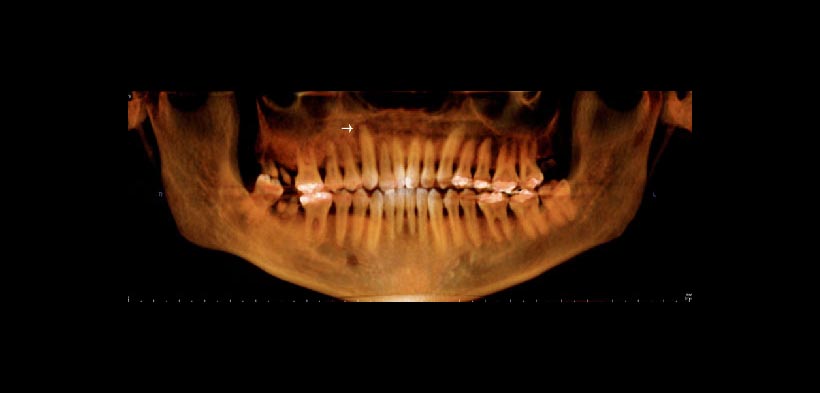

Fig. 1. Reconstrucción panorámica tridimensional de la tomografía computarizada cone beam (CBCT). Reconstrucción tridimensional panorámica que demuestra la apariencia esclerótica generalizada del maxilar superior derecho que se extiende desde el canino superior derecho a la tuberosidad. Nótese la esclerosis anterior a los dientes cariados groseramente (primero y segundo molares) y el defecto vertical en el segundo premolar. La flecha indica el ensanchamiento del espacio para el ligamento periodontal en un diente aparentemente sano (canino superior derecho).